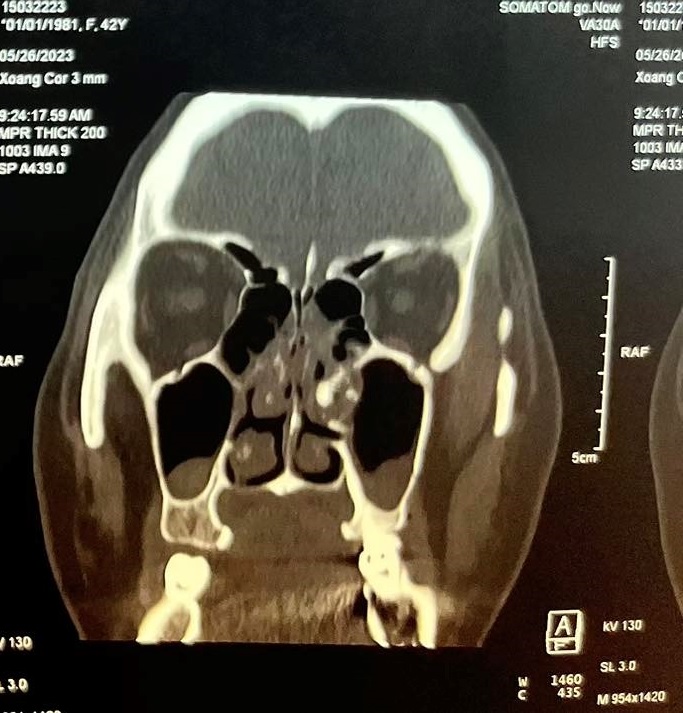

Bệnh nhân nữ, 42 tuổi, không có tiền căn chấn thương vùng hàm mặt trước đó, là công nhân của công ty may mặc, bệnh nhân luôn có cảm giác nghẹt mũi trái, cảm giác dịch nhầy chảy từ mũi xuống họng nhưng không khạc ra được, các cảm giác nhức vùng mặt cùng bên ngày càng rõ nên bệnh nhân đã đi khám nhiều nơi điều trị nhưng bệnh vẫn không thuyên giảmGần đây bệnh nhân xuất hiện thêm đau nhức vùng mắt trái cùng bên nên đã đến khám tại Bệnh viện Quận 4. Qua nội soi thăm khám và thực hiện chụp CT-Scan phát hiện bệnh nhân có cấu trúc mật độ giống xương dính vào thành trong xoang hàm bên trái, đẩy lệch vách mũi xoang về phía vách ngăn gây hẹp hốc mũi bên trái kèm viêm xoang hàm sàng 2 bên và concha bullosa cuốn mũi giữa bên phải gây tắc nghẽn đường dẫn lưu của xoang hàm bên phải

Hình ảnh CT scans mũi xoang